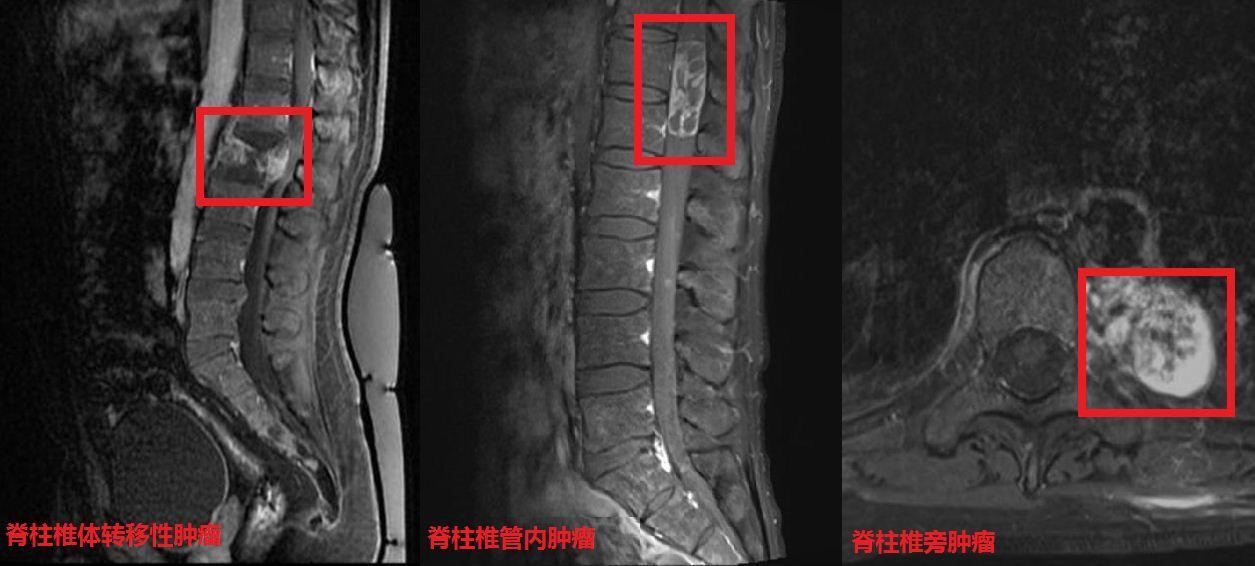

最常见的脊柱肿瘤脊柱转移瘤

【发病率top3】脊柱脊髓肿瘤典型影像